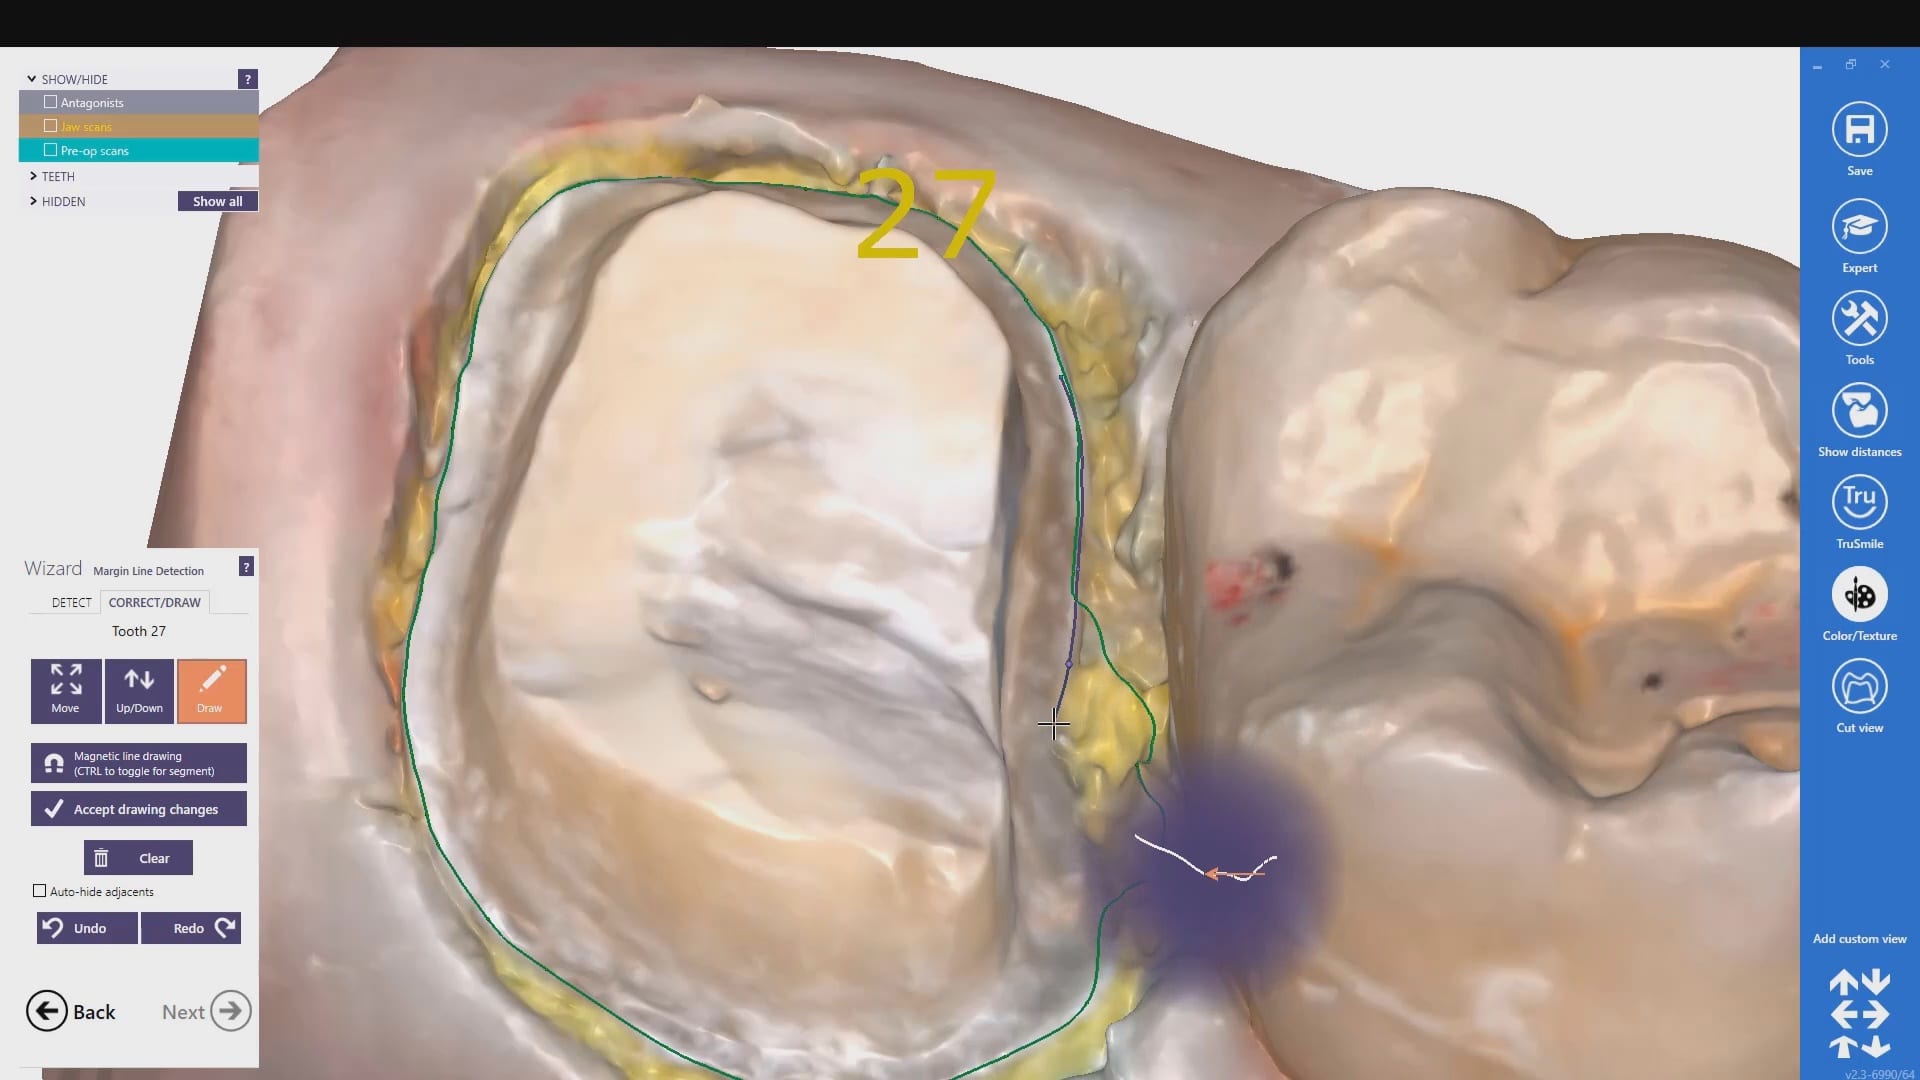

Distal Extension Second Molar Crown Replacement in Copy Mode and With Two Bites

October 28, 2019Every distal extension case I have to accomplish the following: take two bites to make sure my vertical dimension does not change with pre-op and prep images make sure I […]